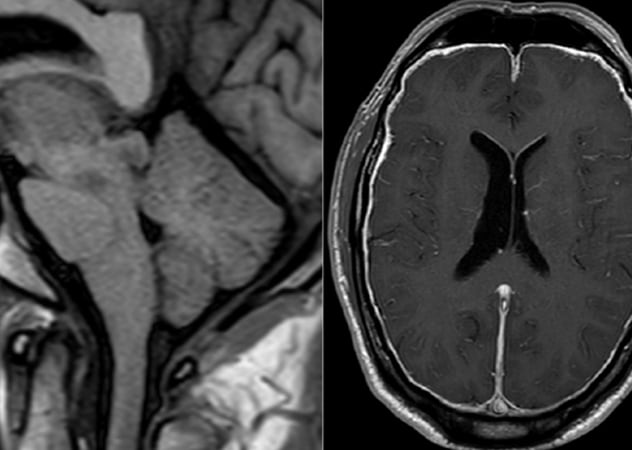

يُظهر التصوير بالرنين المغناطيسي السابق للجراحة لأحد المشاركين في سلسلة حالات مايو كلينك مؤشرات على ضعف الدماغ مع تسطيح الجسر، وقصر المسافة بين الأجسام الحلمية والجسر وانمحاء الكيسات فوق السرج، بالإضافة إلى تعزيز سُمك غشاء الجافية.

يوضح التصوير بالرنين المغناطيسي اللاحق للجراحة الشفاء من حالة ضعف الدماغ وتعزيز السحايا.